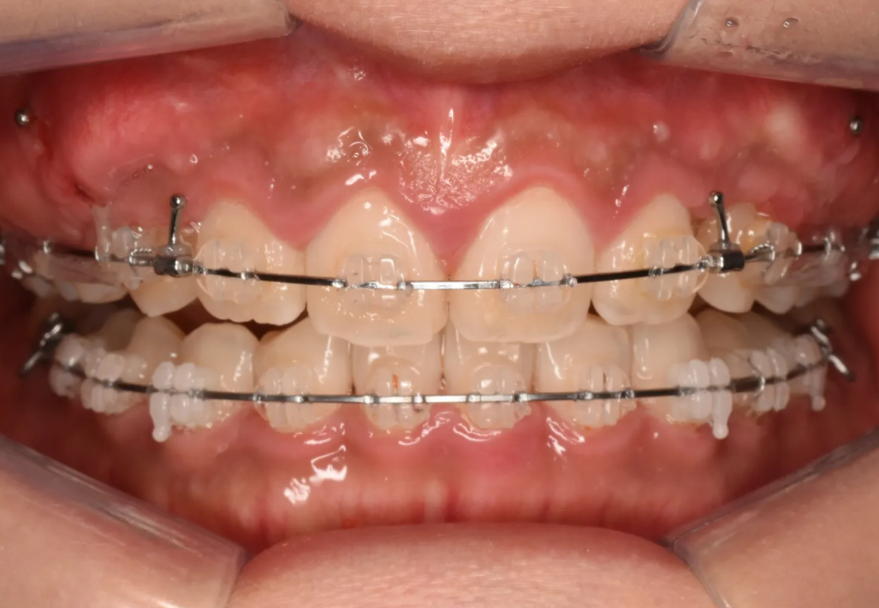

과개교합이 서서히 해소되고 있는 단계. 아래 앞니가 이제 잘 보입니다.